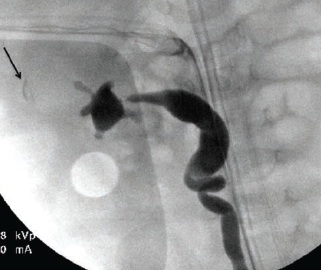

Renal Disease

10/17/2014

Dana A. Weiss, MD; Christopher J. Long, MD; Michael C. Carr, MD, PhD

At 27 weeks’ gestation, a female fetus was found to have left hydronephrosis that was consistent with a left multicystic dysplastic kidney (versus ureteropelvic junction obstruction with a perinephric...